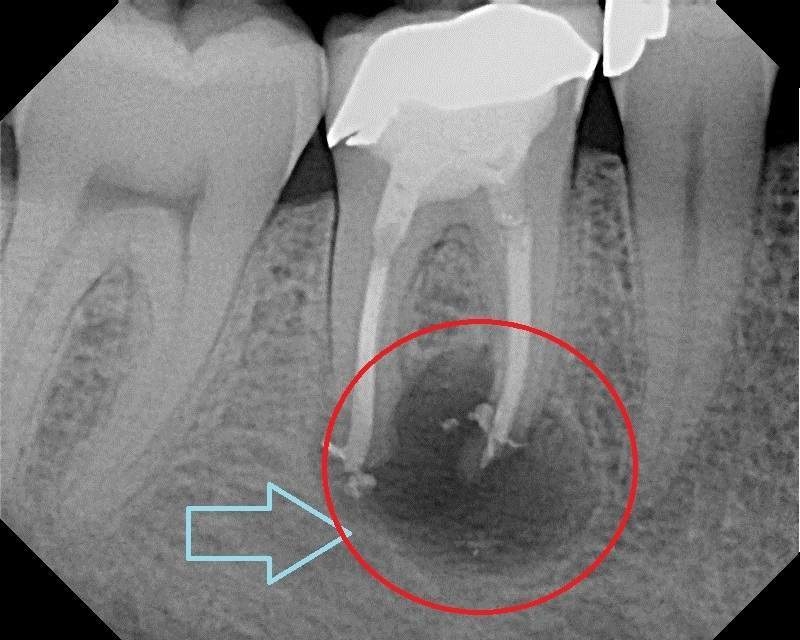

|  |

| Hình ảnh viêm quanh chóp răng trên phim X - Quang |

Áp-xe quanh chóp răng: Nhiễm trùng từ tủy hoại tử lan xuống cuối chân răng, tạo thành một túi mủ (áp-xe), gây sưng nướu, đau nhức dữ dội khi ăn nhai và có thể xuất hiện lỗ rò mủ ra nướu.

Khi đến phòng khám, nha sĩ sẽ chẩn đoán tình trạng viêm tủy thông qua việc hỏi về các triệu chứng, khám lâm sàng, thử nghiệm độ nhạy cảm của răng (thường bằng kích thích lạnh) và chụp phim X-quang để đánh giá mức độ sâu răng và tình trạng quanh chóp răng.